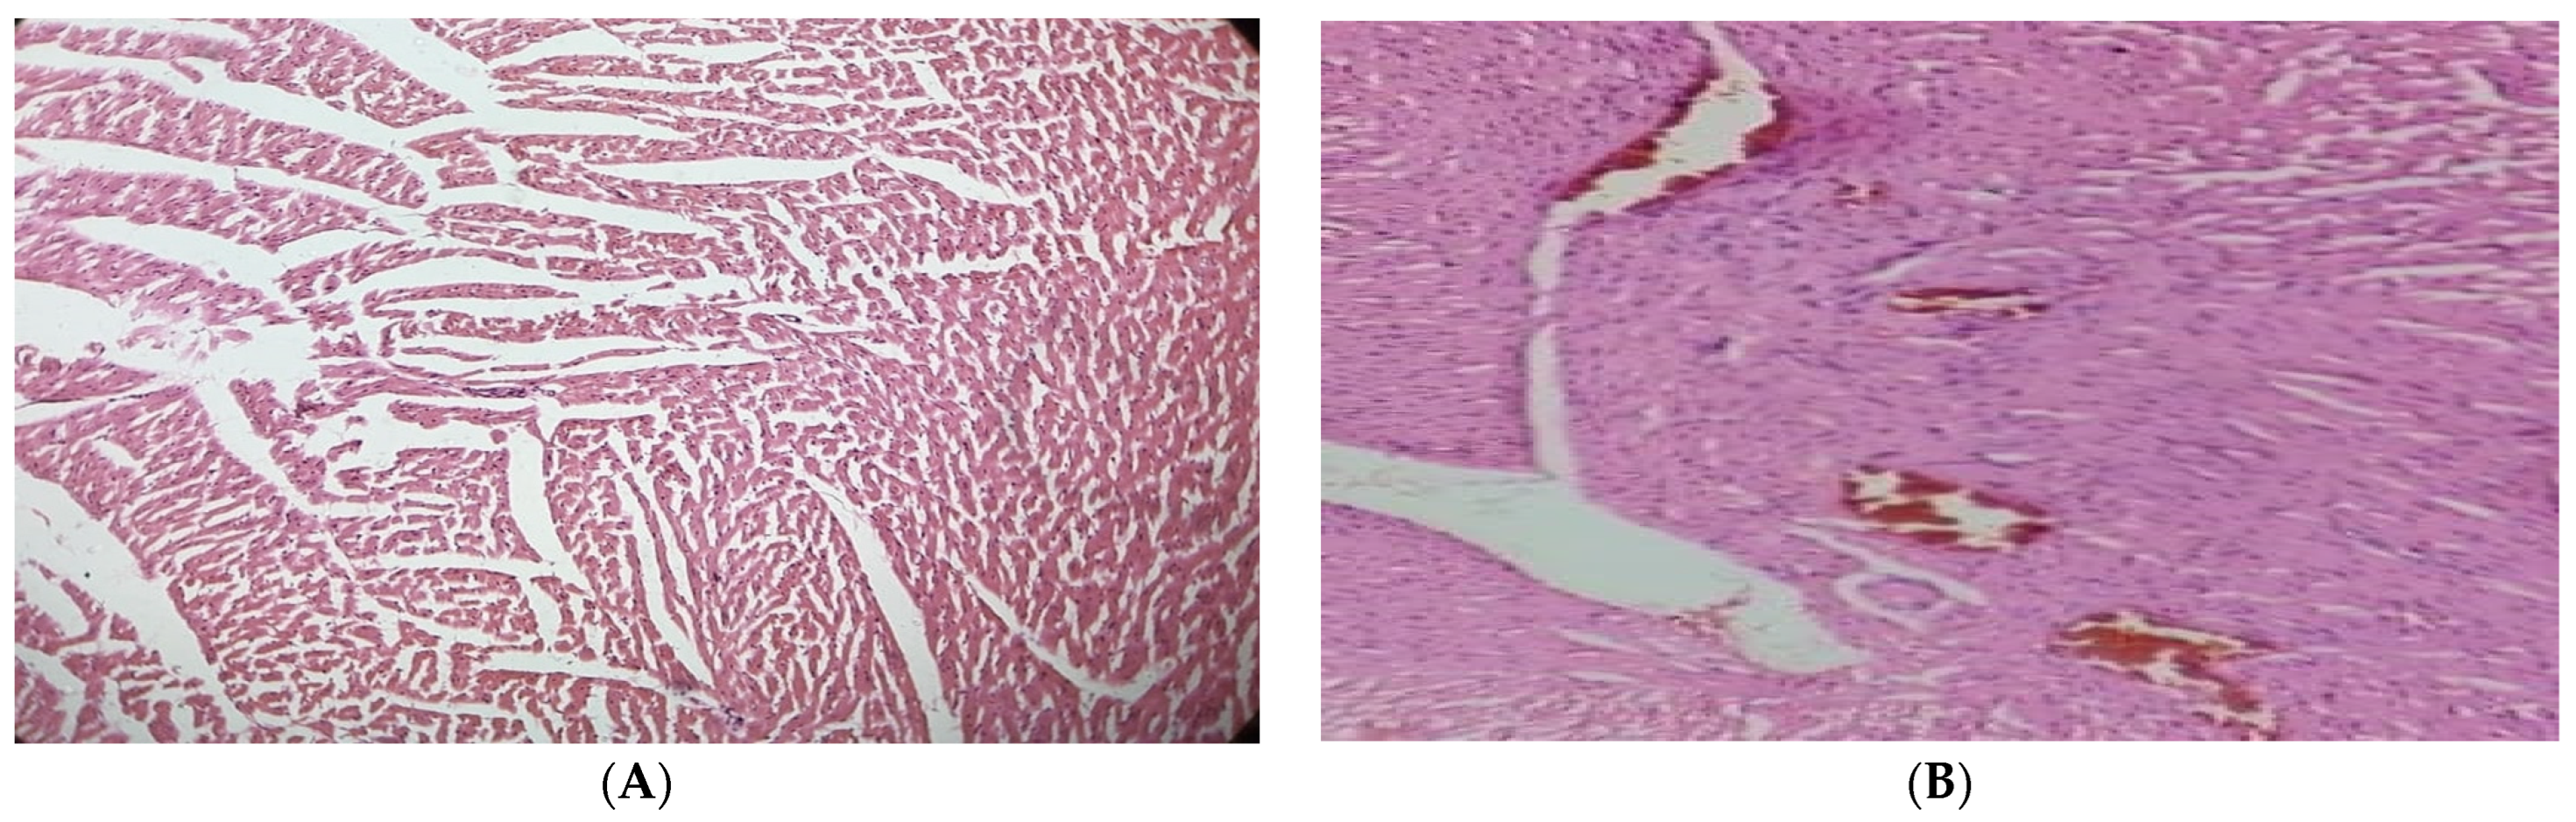

Pancreas

The pancreas of the normal control group displayed typical islets of Langerhans histological characteristics, such as effective nuclei and copious cytoplasm. Compared to the healthy control group, the pancreatic tissue of the alloxan-induced diabetic rats exhibited deterioration, atrophy, inflammatory cellular infiltration, vacuolization, substantial necrotic alterations, congestion, and regression in cell size. In the treatment group of hyperglycemic rats, administering 250 mg/kg of the JSP extract resulted in a substantial reduction (p < 0.05) in cellular destruction, as shown by partial repair of islets and cells. The diabetic group that received 500 mg/kg of the JSP extract responded by producing more (p < 0.05) islet cells overall and fewer necrotic cells, which suggests regeneration. According to the research, islets of Langerhans in the diseased rats administered 500 mg/kg of the phenolic extract displayed a healthy architecture with active cells and no necrotic alterations (Figure 3).

Figure 3.

(A) Pancreas of the normal control group with normal histological islets of Langerhans, including active nuclei. (B) Pancreas of the diabetic control group with inflammatory and necrotic alteration in β-cells, cellular infiltration, vacuolization, congestion, and atrophy. (C) Pancreas of the 250 mg/kg-treated group with improvement in cellular damage and congestion. (D) Pancreas of the 500 mg/kg-treated group with an increased volume of islet cells and regeneration of β-cells.